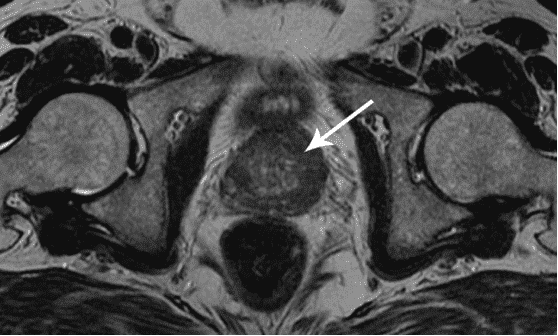

أستطيع أن أرى الرجال الذين يزورونني بسبب التهاب البروستاتا أو تضخم البروستاتا الحميد كل يوم. في الواقع، هذه الأمراض هي حالات ما قبل سرطانية غدة البروستاتا.

كما ترى، ترتبط هذه المشكلات ارتباطًا مباشرًا بممارسة الجنس بانتظام. عندما يتوقف الرجل عن ممارسة الجنس بانتظام، تصاب غدة البروستاتا بالاحتقان، ونتيجة لذلك، يتسبب ذلك في حدوث التهاب ويوقف إنتاج الهرمونات المهمة. بدون علاج طويل الأمد، يتطور التهاب البروستاتا إلى تضخم البروستاتا الحميد الذي يتحول بعد ذلك إلى سرطان.

في الواقع، هرمون التستوستيرون هو هرمون الاستثارة الذكري. كلما زاد إنتاج هرمون التستوستيرون في جسم الرجل، كلما زادت رغبة الرجل في المرأة، زادت رجولته. عند الرجال، تصل مستويات هرمون التستوستيرون إلى ذروتها في سن 18-22، ثم يبدأ إنتاجه في الانخفاض: في البداية، ينخفض ببطء، ولكن بعد ذلك ينخفض بشكل أسرع وأسرع وهكذا، عندما تكون مستويات هرمون التستوستيرون منخفضة للغاية، تفقد رجولتك ويبدأ جسمك في الشيخوخة.